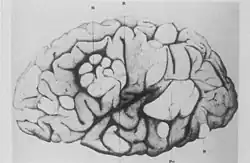

A side profile sketch of a brain, with parts indicated by a letter code. The normal convolutions of the brain are distorted in these areas, forming lumps or thickened folds.

Esclerosis tuberosa cerebral que muestra circunvoluciones escleróticas e hipertróficas.

Bourneville y Édouard Brissaud examinaron a un niño de cuatro años en el hospital Bicêtre. Al igual que antes, este paciente tenía tubérculos corticales, epilepsia y dificultades de aprendizaje. Además, tenía un soplo cardíaco y, en la autopsia, se encontraron pequeños tumores duros en las paredes ventriculares del cerebro (nódulos subependimarios) y pequeños tumores en los riñones (angiomiolipomas).[16]